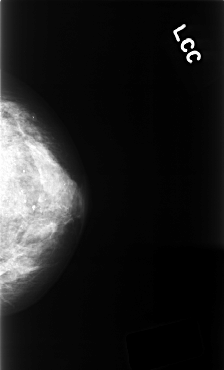

C_0394_1.LEFT_CC

LEFT_CC LINES 4800 PIXELS_PER_LINE 2904 BITS_PER_PIXEL 12 RESOLUTION 50 NON_OVERLAY